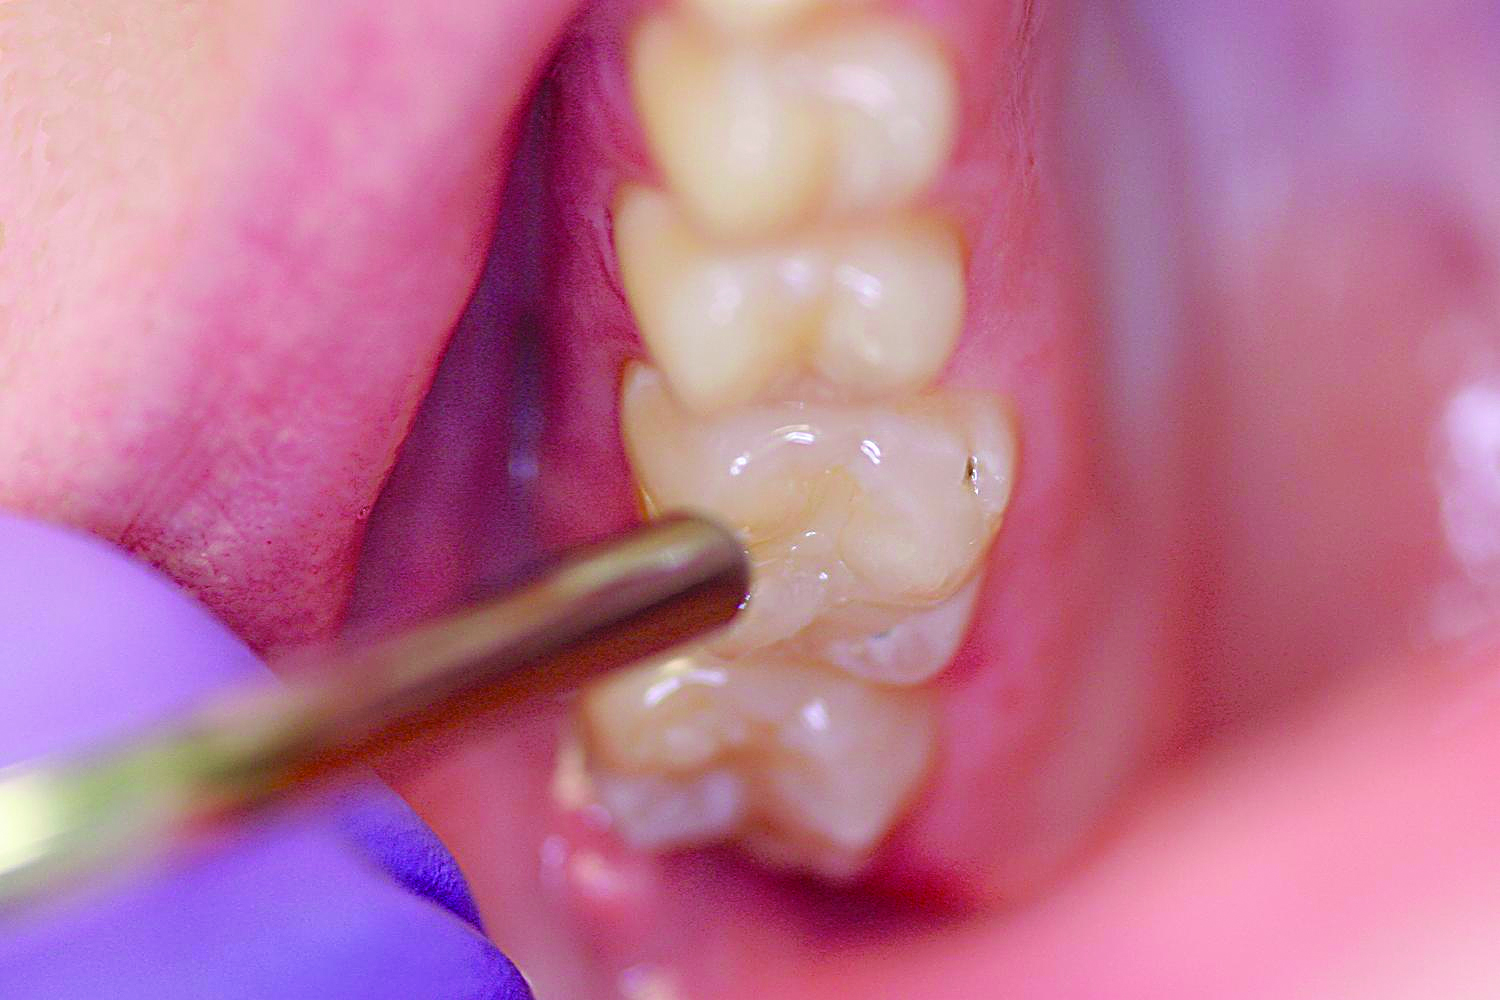

9. Apply the sealant over the pits and fissures (Figure 10). Avoid over manipulation to prevent producing air bubbles. Cover all the pits and fissures, but do not overfill to a high, flat surface.

Fig 11. Once the sealant is polymerized, evaluate the sealant with an explorer and check for a hard, smooth surface and retention.